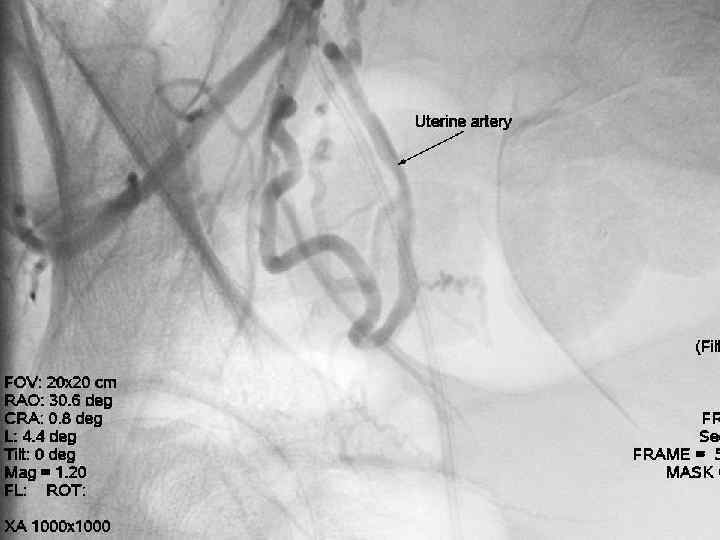

Эмболизация маточных артерий Показания к проведению ЭМА в акушерстве: - Высокий риск кровотечения в родах (предлежание плаценты, аномалии прикрепления плаценты, многоплодная беременность) - Гипо- и атонические кровоточения в раннем послеродовом периодах По данным литературы эффективность метода ЭМА при лечении акушерских кровотечений достигает 94, 9 %.

Эмболизация маточных артерий • - • Эмболизация проводится чрезкатеторной пункцией a. femoralis в верхней части бедра. Прокол осуществляется под местной анестезией. - В сосуд через интродъюсер вводят катетер, диаметром 1, 2 мм и проводят его под контролем рентгенотелевидения в маточные артерии. Продвижение катетера по сосудам безопасно и не вызывает никаких ощущений.

Эмболизация маточных артерий - • После установки катетера через него вводятся эмболизационные частицы. Среднее время продолжительности процедуры 15 -20 минут. В редких случаях особенности строения маточной артерии могут потребовать большего времени для установки катетера. - Операция проводится ангиохирургом.